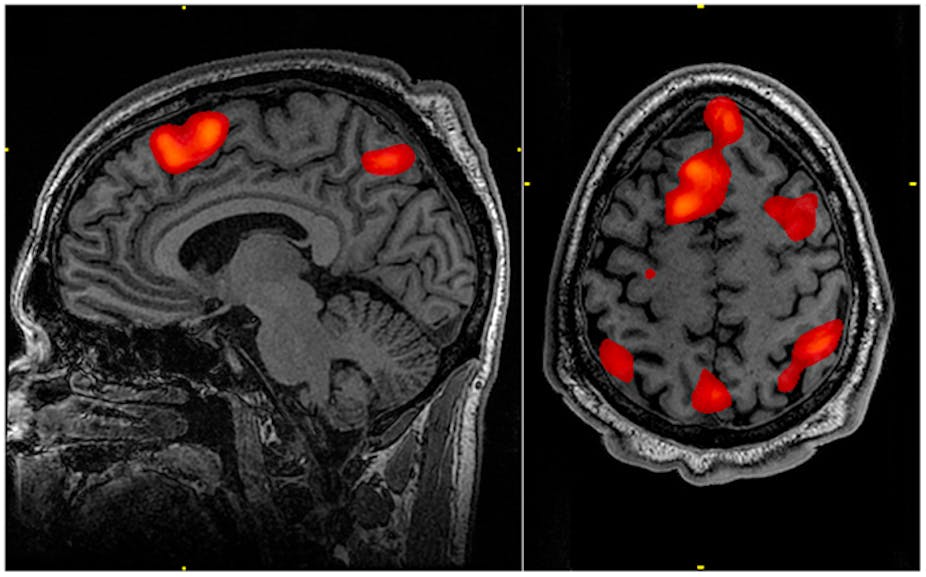

But now there is a technology that enables us to “read the mind” with growing accuracy: functional magnetic resonance imaging (fMRI). It measures brain activity indirectly by tracking changes in blood flow – making it possible for neuroscientists to observe the brain in action. Because the technology is safe and effective, fMRI has revolutionised our understanding of the human brain. It has shed light on areas important for speech, movement, memory and many other processes.

As a subject in these studies, you would typically have to answer a series of questions. Some of your answers would be truthful, some would be lies. The computer model is told which ones are which in the beginning so it gets to know your “brain signature of lying” – the specific areas in your brain that light up when you lie, but not when you are telling the truth.

Afterwards, the model has to classify new answers as truth or lies. The typical accuracy reported in the literature is around 90%, meaning that nine out of ten times, the computer correctly classified answers as lies or truths. This is far better than traditional measures such as the polygraph, which is thought to be only about 70% accurate. Some companies have now licensed the lie detection algorithms. Their next big goal: getting fMRI-based lie detection admitted as evidence in court.